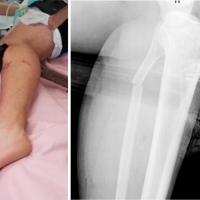

A 34-year-old female presented with dull low back pain radiating to bilateral lower limb and paresthesias in the lower limb of 2 years duration. It was associated with episodic palpitation, perspiration, and occasional headache for 2 years. Medical history was positive for two episodes of hypertensive urgency which required inpatient admission and management. However, at no time, further evaluation was carried out to investigate the etiology for the hypertension. On general examination, she was a female in her early 30s averagely build and nourished. Vitals were within normal limits with the exception of few episodes of hypertension where the BP reached maximum of 220/140 mmHg. Low back pain was not associated with any spinal tenderness and neurological examination was unremarkable. Laboratory investigations revealed that plasma-free normetanephrine was 4555pg/ml (Normal= 0–196). Plain radiographs of the lumbosacral spine showed scalloping of the anterior border of L1 vertebra and degenerative changes lower down at L4-L5 (Fig. 1). Magnetic resonance imaging (MRI) of the lumbar spine revealed heterogeneously enhancing retroperitoneal lesion at L1 with areas of necrosis (Fig. 2-4). Both adrenal glands were unremarkable. Computed tomography (CT) abdomen and pelvis were suggestive of hyperenhancing lobulated mass measuring 29× 49 mm axially closely abutting abdominal aorta for more than 90° but <180° with loss of intervening fat planes at L1 with scalloping and anterior destruction of L1 vertebral body. Positronemission tomography (PET) scan was suggestive of metabolically active lesion seen at L1 and L2 vertebra (Fig. 5). Scintigraphic evidence of metaiodobenzylguanidine (MIBG) avid mass in upper abdomen suggesting paraganglioma was found on iodine-123-MIBG scan (Fig. 6). The patient required pre-operative optimization of blood pressure with the combination of alpha-blockers and beta-blockers in optimum dosage before surgical resection. The patient underwent angioembolization before the surgery in view of high vascularity to reduce the intraoperative blood loss. Bilateral feeders from lumbar arteries were embolized with 100–200µ particles. Surgical approach was planned as a staged procedure. In the first stage in prone position under general anesthesia, a midline posterior approach was used. Pedicular screw instrumentation (except at L1) and fusion were performed from D11 to L3 (Fig. 7). In the second stage, the patient underwent excision of tumor mass with L1 corpectomy and anterior reconstruction with an expandable titanium cage and tricortical onlay graft by a retroperitoneal approach in the right lateral position (Fig. 8-10). The graft was harvested from the left iliac crest. Intraoperatively, there were fluctuations of blood pressure during tumor removal which was handled well with inotropic support. Histopathology report was suggestive of cells in nests, “Zellballen”(ball of cells) pattern. On immunohistochemistry, tumor cells were positive for chromogranin A, S-100, Cyclin-D1, and weakly positive for synaptophysin. Nuclei showed atypia; however, mitotic activity was absent. The patient was immobilized for 3 weeks in bed following which she was mobilized with a Taylor’s brace. The patient remained neurologically intact following the second stage of surgery and is at present asymptomatic 8 months following the surgery with no complaints of backache, palpitations, or hypertension.